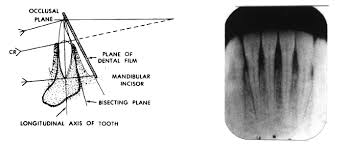

incorrect film placement

incorrect horizontal angulation/ overlap

vertical angulation too steep/foreshortened

verticlal anglulation too flat/ elongation